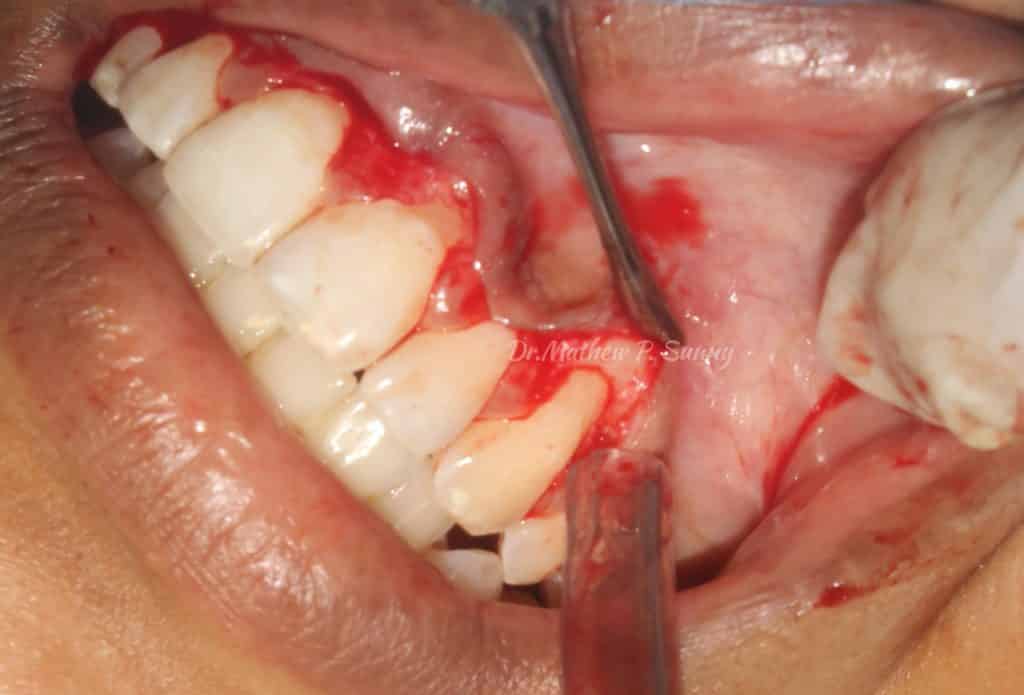

same done for right canine..